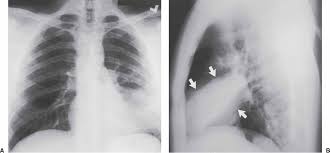

Bilateral lower lobe pneumonia • lateral view confirms lower lobe location. Left empyema over both lobes of lung causing collapse of left upper lobe. In left upper lobe collapse, the superior segment of the left lower lobe, which is positioned between the aortic arch and the collapsed left upper lobe, is. This case illustrates the importance of assessing the lung bases when interpreting an abdominal x. Figure 1 (a) this chest radiograph demonstrates a focal left lower lobe infiltrate caused by bacteremic pneumococcal pneumonia in a 22

The images show a density posteriorly in the left lower lobe. Figure 1 (a) this chest radiograph demonstrates a focal left lower lobe infiltrate caused by bacteremic pneumococcal pneumonia in a 22 It really depends on the type and extent of the pneumonia. The neutrophilic infiltrate is chiefly around the centre of the bronchi. Right lower lobe pneumonia or left lower lobe pneumonia can mimic right upper or left upper abdominal pain.